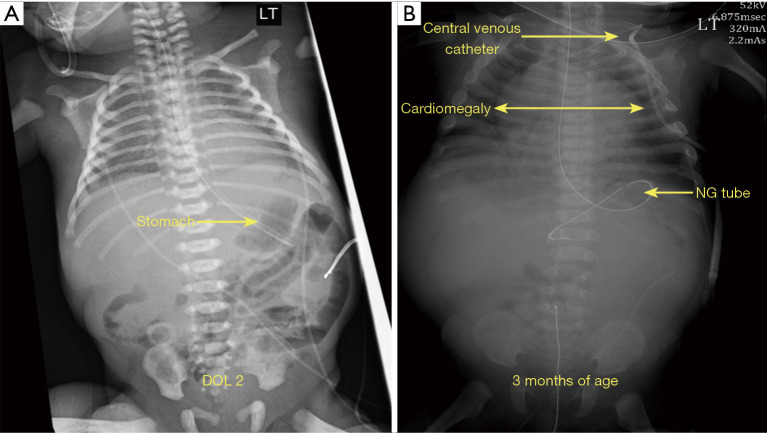

Case description: We describe the salient features of a newborn with CNF and multiple fetal anomalies based on clinical risk factors discovered by ultrasound (US) and X-rays, which include cardiomegaly, polycystic kidney disease, and renal dysplasia. Biochemical tests showed substantial proteinuria and excess protein in the urine detected at birth; this condition caused albuminuria, hypoalbuminemia, edema, and additional symptoms. The patient underwent treatment to reduce the risks of proteinuria, hypertension, infection, and other symptoms. The next generation sequencing (NGS) analysis revealed that the infant had five previously unreported heterozygous missense variants classified as VUS in NPHS1, NUP160, ALG1, and CRB2. The NPHS1 c.2150A>G and CRB2 c.1654G>T may lead to defects in the CTCF (CCCTC binding factor) and exonic splicing enhancer (ESE) motifs, respectively, which could account for the observed clinical features in the newborn.